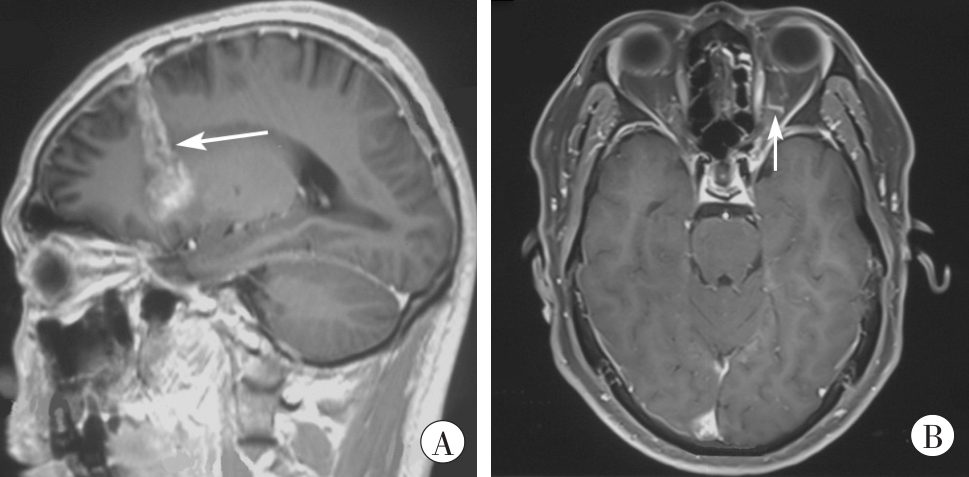

眶内眼球外异物致视神经损伤2例

关键词: 法医学, 视神经损伤, 颅脑损伤, 眶内眼球外异物, 视力下降